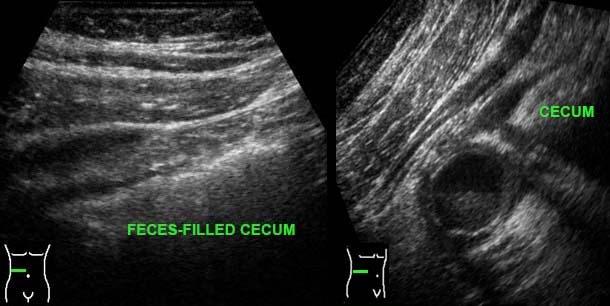

Trong viêm ruột thừa sau manh tràng (mũi tên), manh tràng thường bị đẩy về phía trong bởi đầu dò siêu âm, khiến ruột thừa (mũi tên) có vẻ nằm ở phía bên ngoài manh tràng thay vì phía sau nó.

Một khả năng khác để quan sát ruột thừa trong viêm ruột thừa sau manh tràng là đặt đầu dò ở vùng hông phải, nhờ đó tránh được manh tràng chứa đầy hơi và phân.

Để tìm ruột thừa, trước tiên có thể hữu ích khi xác định van hồi manh tràng (xem thêm Siêu âm đường tiêu hóa: giải phẫu bình thường).

Gốc ruột thừa thường được tìm thấy cách đó 3 cm về phía đuôi, nơi nó xuất phát từ cực manh tràng ở mặt trong.